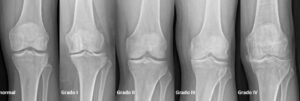

El diagnóstico de la artrosis de rodilla es sencillo. Se basa en el interrogatorio que realiza el médico al paciente sobre las características de los síntomas, seguido de una exploración de la articulación de la rodilla, con la evaluación de los movimientos de la misma.El diagnóstico se confirma mediante la práctica de una radiografía de las rodillas, en las que el médico puede ver los signos inconfundibles y característicos de la artrosis, como estrechamiento del espacio articular, cambios en el hueso y la formación de espolones óseos (osteofitos)..